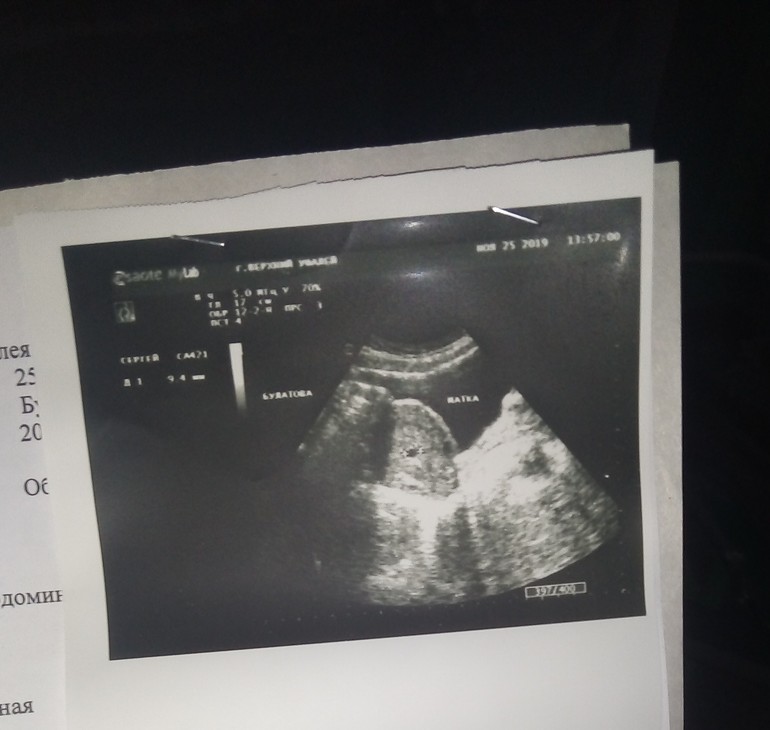

Верхний Уфалей

У меня такой же срок,токсикоза нет,ничего не где не болит,спину только тянет иногда,ранее живот только болел,щас все прошло,тоже на днях делали УЗИ